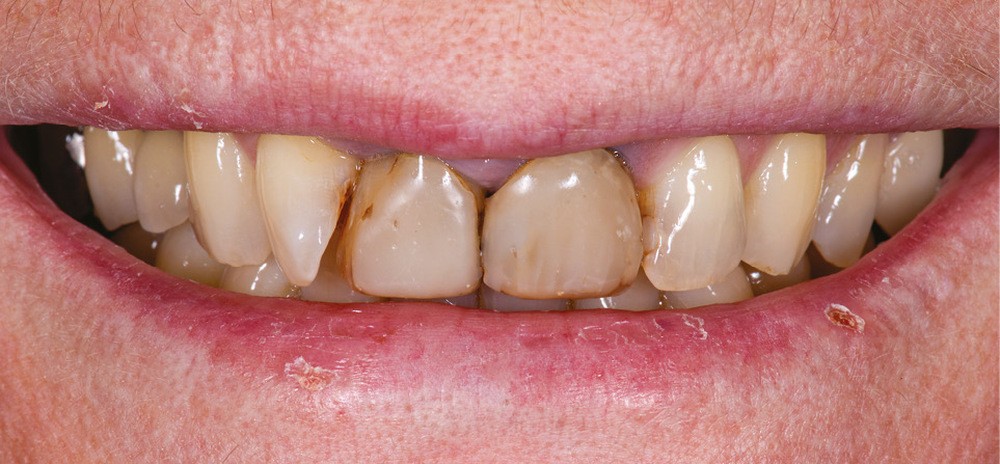

Présentation du cas (fig. 1 et 2)

Une patiente de 55 ans se présente pour une prise en charge esthétique de son sourire. Sa demande regroupe à la fois la teinte, l’encombrement incisivo-canin et l’asymétrie des incisives centrales.

Les deux incisives centrales ont été traitées endodontiquement plusieurs années auparavant et restaurées par des composites directs.

Le contrôle de plaque est insuffisant et nous notons une perte d’attache entre 12 et 11.

La patiente refuse d’emblée tout traitement orthodontique, même par aligneurs.